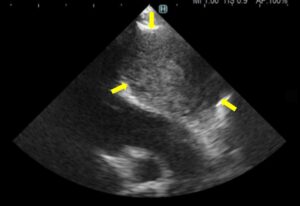

心臓血管肉腫は通常、心タンポナーデに関する症状である活動不耐、呼吸困難、腹水貯留、不整脈等を示します(画像1・2)。

画像1:右心耳領域の腫瘤:血管肉腫を疑う